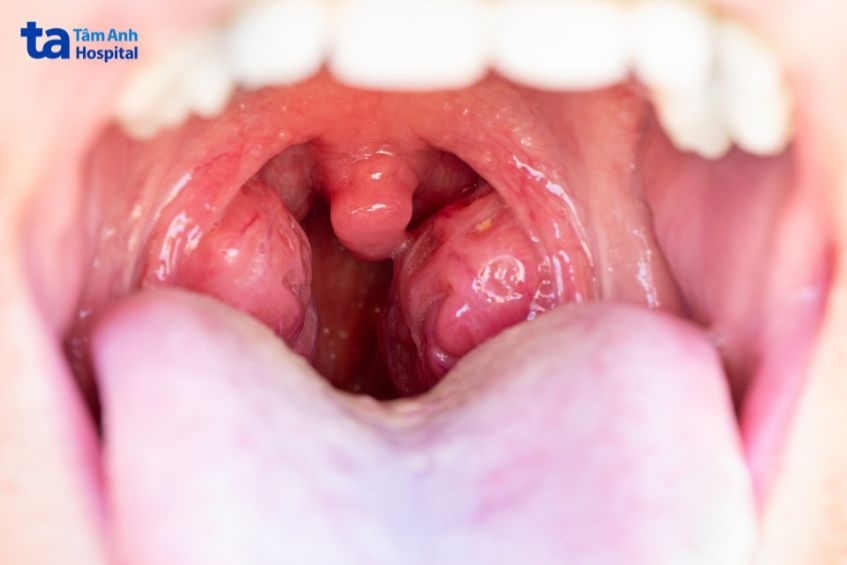

Viêm họng hạt mạn tính là thể viêm họng kéo dài và tái phát nhiều lần, gây tổn thương ở niêm mạc họng. Tình trạng này xảy ra khi niêm mạc họng bị kích thích thường xuyên hoặc kéo dài, khiến các tế bào lympho (tế bào miễn dịch) ở thành họng tăng sinh và phì đại, hình thành nên các hạt nhỏ lấm tấm phía sau thành họng, gọi là “hạt lympho”.

Nổi hạt phía sau họng.

Các hạt lympho hình thành từ mủ sẽ khá đa dạng về kích thước và màu sắc, thường có màu trắng hoặc vàng.

Triệu chứng viêm họng hạt mạn tính thường thấy là đau họng, niêm mạc sưng, nổi các hạt phía sau họng